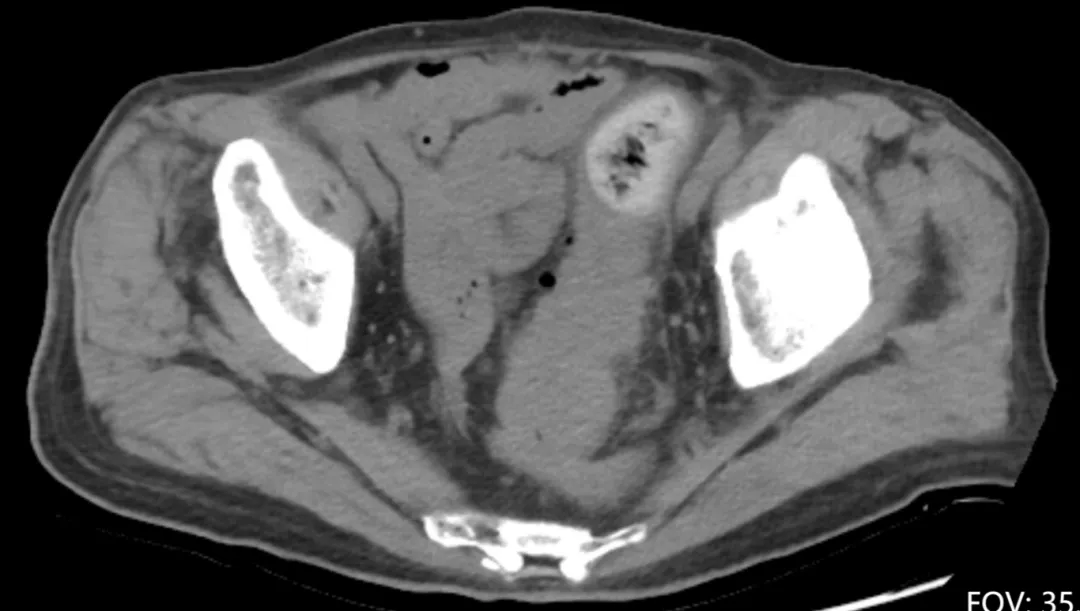

腹盆腔平扫CT显示直肠乙状结肠连接部巨大占位伴周围渗出